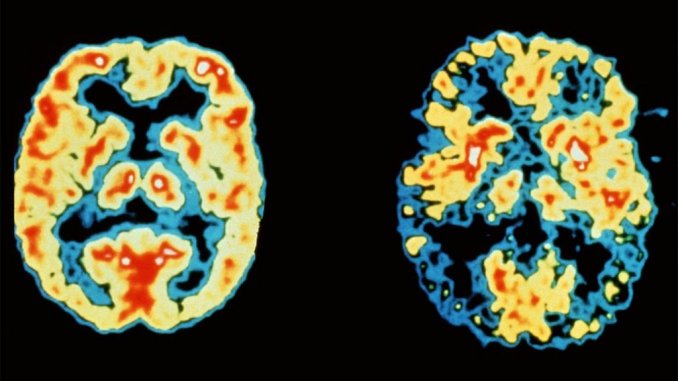

阿茲海默症是失智症的一種,佔所有失智症患者的50-70%,全球患者人數多達5000萬人。然而,迄今在市面上仍然沒有任何藥物可以有效地治療阿茲海默症。在未來,隨著全球人口老化,這疾病將成為政府和政策制定者所面臨的一個嚴重問題。

科學家認為,大腦中 β 澱粉樣蛋白質斑塊沉積與阿茲海默症息息相關。因此,世界各地的研究員都在致力尋找方法來消除或減少大腦中的 β 澱粉樣蛋白質斑塊。而最近,來自德國慕尼克工業大學(Technical University of Munich)的科學家發表了一篇論文,論文聲稱,使用 BACE 抑制劑藥物可以減少小鼠大腦中 β 澱粉樣蛋白的含量,恢復正常神經細胞的功能,並能顯著提高患者的記憶力。

觀察結果顯示,小鼠的 β 澱粉樣蛋白含量和大腦功能恢復正常、大腦中過度活躍的神經細胞數量減少。這項研究的一個重大發現是,經過療法後,老鼠的記憶力有顯著提高,它們能夠記住和定位一個藏在水中迷宮裡的隱藏平臺,速度與正常小鼠相同。